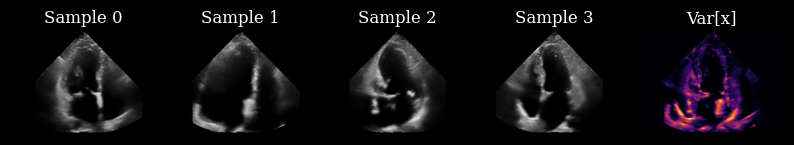

Initially, we have not yet acquired any measurements, so we draw samples from the prior to drive our actions.

prior_samples = model.sample(n_samples=n_prior_samples, n_steps=n_unconditional_steps, verbose=True)

scan_converted_prior_samples = scan_convert(

data=keras.ops.squeeze(prior_samples, axis=-1), **parameters

)["data"]

posterior_variance = ops.nan_to_num(ops.var(scan_converted_prior_samples, axis=0))

fig, _ = plot_image_grid(

list(scan_converted_prior_samples) + [translate(posterior_variance, range_to=(-1, 1))],

titles=[f"Sample {i}" for i in range(n_prior_samples)] + ["Var[x]"],

vmin=-1,

vmax=1,

cmap=["gray"] * n_prior_samples + ["inferno"],

)